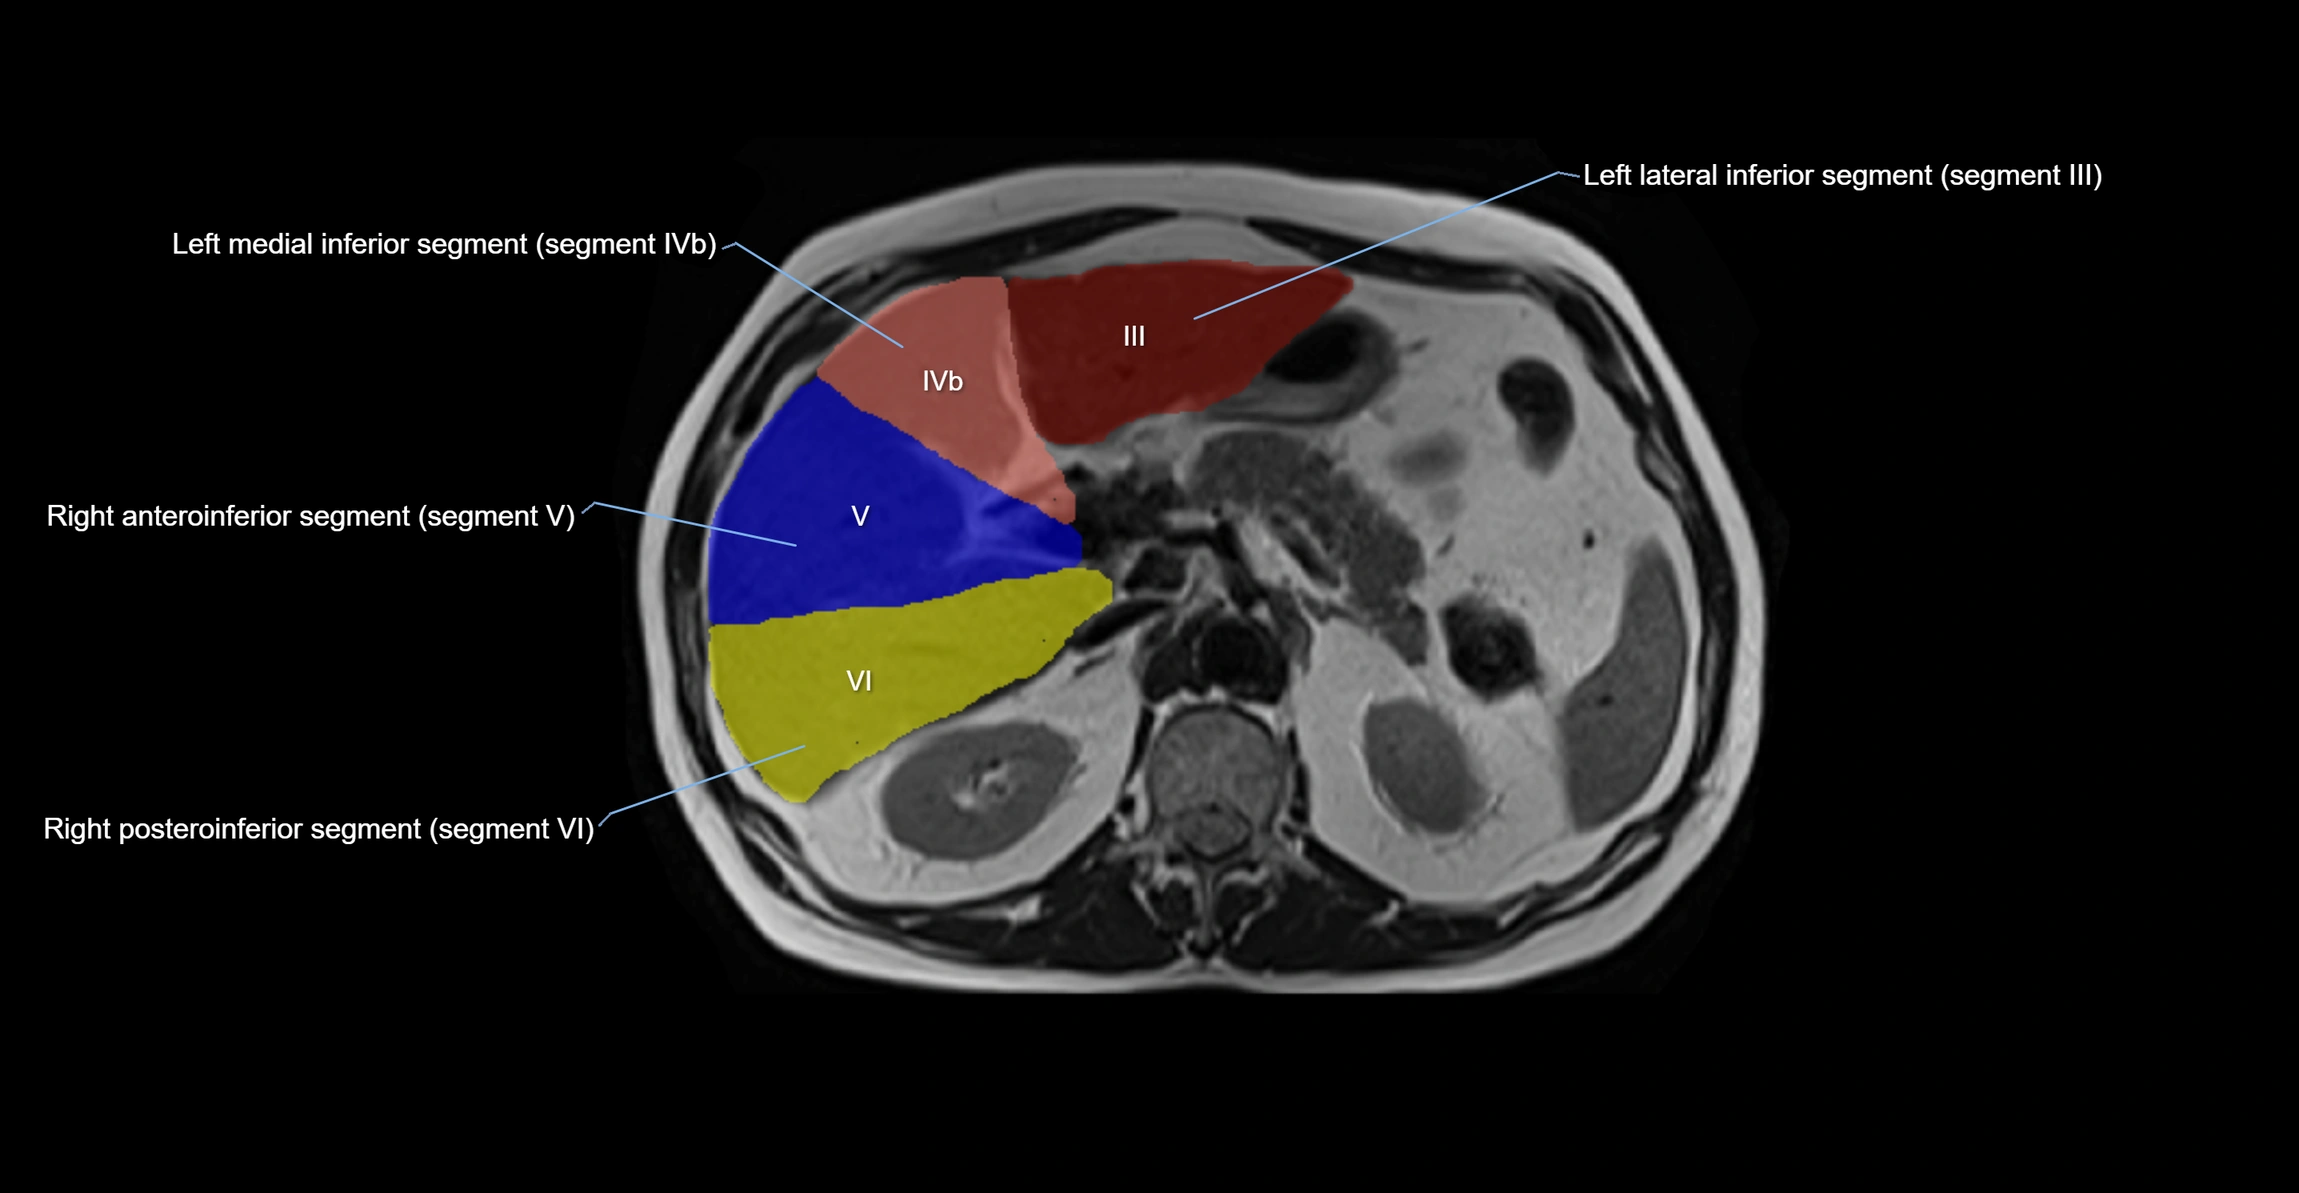

MRI image

image